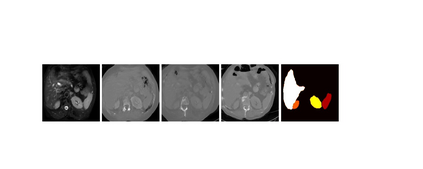

This work presents a novel framework CISFA (Contrastive Image synthesis and Self-supervised Feature Adaptation)that builds on image domain translation and unsupervised feature adaptation for cross-modality biomedical image segmentation. Different from existing works, we use a one-sided generative model and add a weighted patch-wise contrastive loss between sampled patches of the input image and the corresponding synthetic image, which serves as shape constraints. Moreover, we notice that the generated images and input images share similar structural information but are in different modalities. As such, we enforce contrastive losses on the generated images and the input images to train the encoder of a segmentation model to minimize the discrepancy between paired images in the learned embedding space. Compared with existing works that rely on adversarial learning for feature adaptation, such a method enables the encoder to learn domain-independent features in a more explicit way. We extensively evaluate our methods on segmentation tasks containing CT and MRI images for abdominal cavities and whole hearts. Experimental results show that the proposed framework not only outputs synthetic images with less distortion of organ shapes, but also outperforms state-of-the-art domain adaptation methods by a large margin.